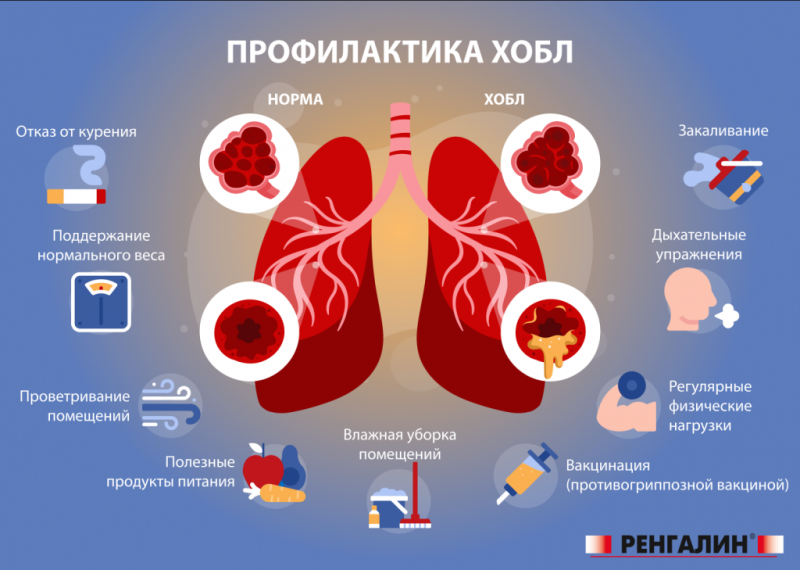

- Отказ от курения: это самый важный шаг для замедления прогрессирующего заболевания.

- Реабилитация: дыхательная гимнастика, лечебная физкультура, кислородная терапия улучшают качество жизни пациентов.

- Профилактика обострений: важно соблюдать рекомендации врача, избегать контакта с раздражителями и вовремя лечить простудные заболевания.